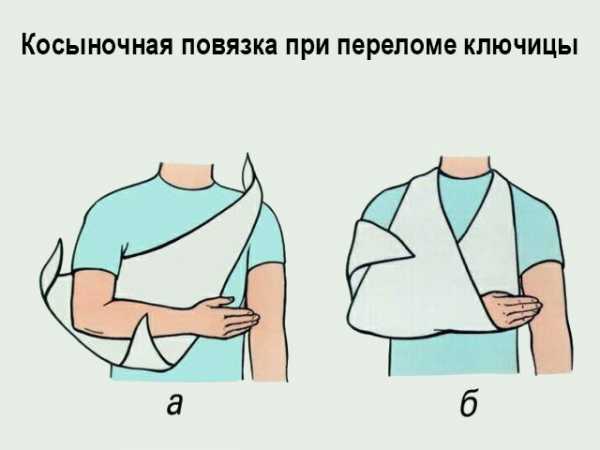

Но что делать, если бинтов, подручных средств рядом не оказалось? Самым простым средством иммобилизации является косыночная повязка. Хотя она не так надёжно фиксирует верхнюю конечность, как другие способы иммобилизации, но всё же надеяться на неё можно. Такой метод позволяет избежать провисания: то есть мышцы, которые крепятся к ключице, не будут натягиваться, что не приведёт к смещению осколков кости, повреждению мягких тканей, сосудов, нервов.

Для повязки хорошо применять косынку, но подойдёт любой квадратный кусок ткани с длиной стороны примерно 1 метр. Квадрат складывается по диагонали для образования треугольника. На большую сторону треугольника укладывается запястье со стороны повреждения.

Длинные концы косынки завязываются за шеей, но надо натянуть косынку, рука должна быть комфортно подвешена под углом 90 градусов к плечевой кости. Свободный край косынки распределяют, закрепляют булавкой к поверхности повязки.

Первая помощь

Первая помощь заключается в подвешивании конечности на косыночную повязку, сгибании ее в локтевом суставе и прибинтовывании к телу. Не следует самостоятельно пытаться устранить смещение путем резких рывков или движений пострадавшей конечностью – это может стать причиной вторичного смещения отломков, повысить угрозу возникновения осложнений.

- иммобилизацию – фиксирующую повязку накладывают для предупреждения смещения. В домашних условиях делают крестообразную повязку, используя бинт. Повязка при переломе ключицы обязана быть тугой, иначе в ней не будет толку. Сначала оборачивают здоровую ключицу, бинт переходит по спине и задействует пораженное плечо. Наложение повязки при переломе ключицы удается сделать не всем. При отсутствии опыта лучше не трогать больного, тем более, если есть подозрение на смещение. Руку можно зафиксировать обычной косынкой, завязав концы за шеей.